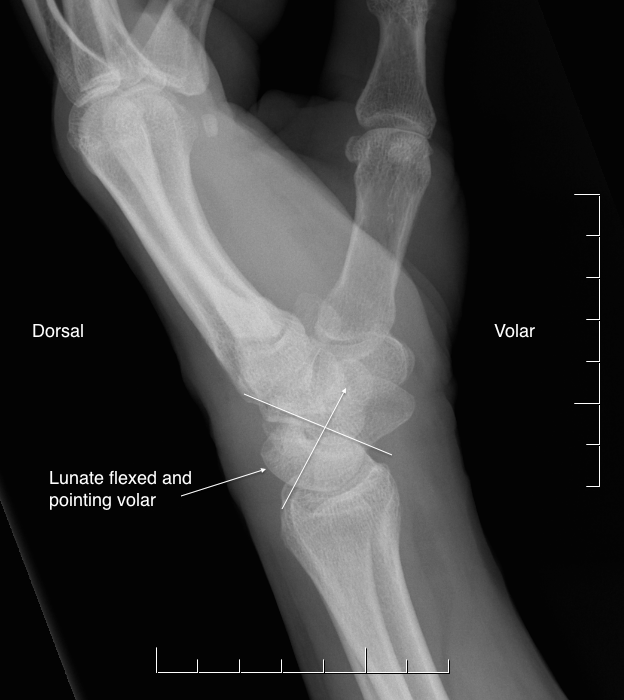

17. 손등 사이 분절 불안정성(DISI)과 손바닥 사이 분절 불안정성(VISI)에 대해 정의하라.

DISI와 VISI는 손목의 측면 방사선 사진 상에서 월상골의 기울임에 의한 수근골의 불안정성을 의미한다. DISI는 월상골이 손등 방향으로 기울어져 있는 것을 말하며, VISI는 월상골이 손바닥 방향으로 기울어져 있는 것을 말한다.

△ A 그림은 DISI(Dorsal intercalated segmental instability)

B 그림은 VISI(Volar intercalated segmental instability)

DISI (이미지 출처 : http://www.emergucate.com/)

VISI (이미지 출처 : http://oxfordorthopaedics.co.nz/service/hands-soft-tissue-injuries/)